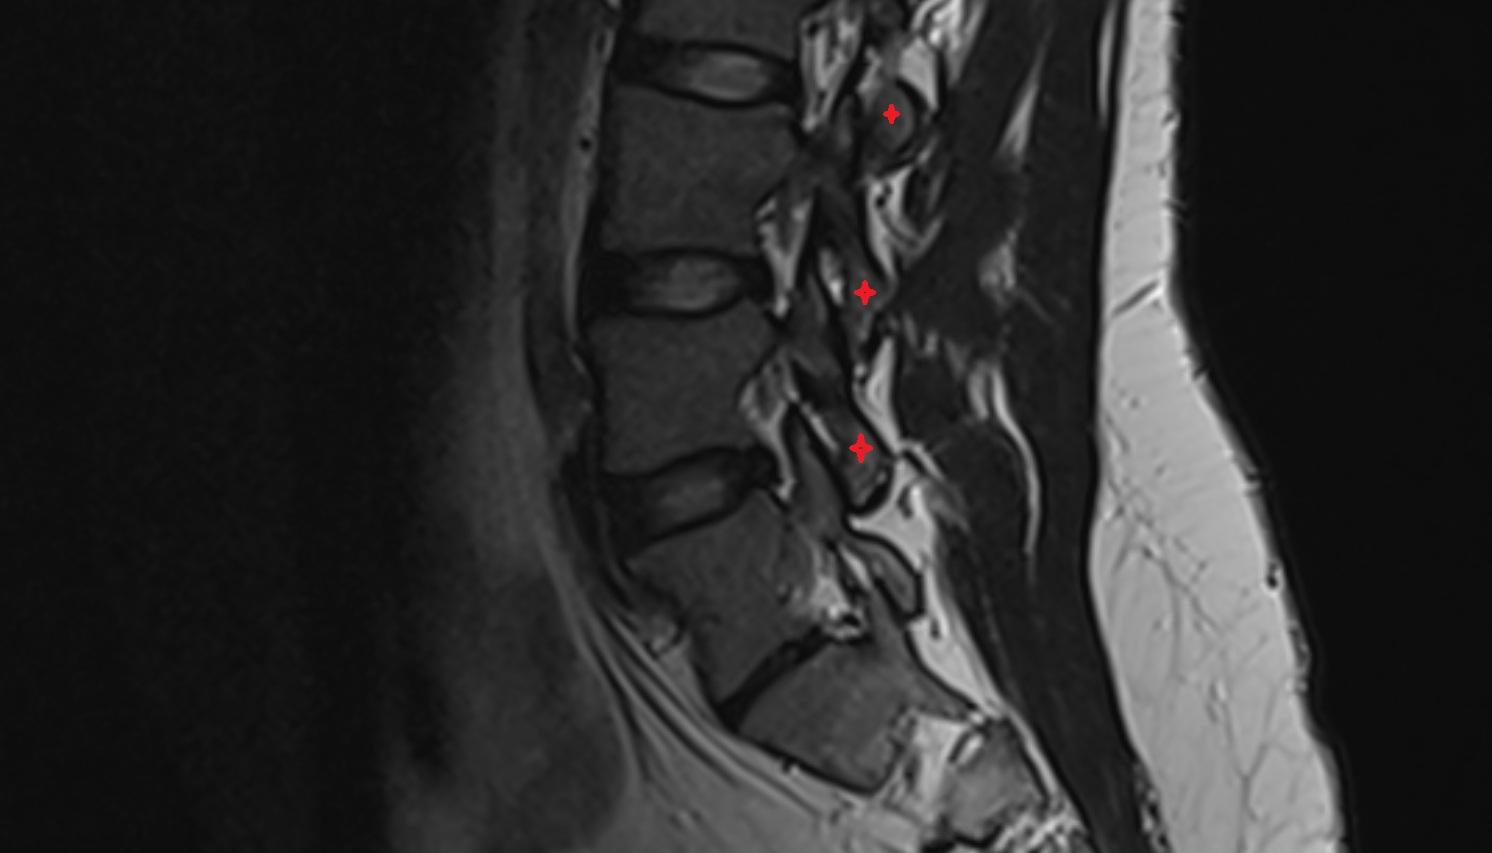

- Traversing nerve root of spinal nerve

- Exiting nerve root of spinal nerve

- Exiting nerve root of spinal nerve S1

- Traversing nerve root of spinal nerve S1

- Traversing nerve root of spinal nerve S2

- Dorsal traversing nerve root

- Ventral traversing nerve root

- Dorsal exiting nerve root

- Ventral exiting nerve root